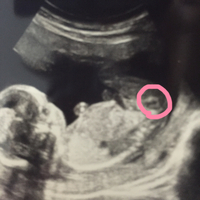

妊娠15週目のエコー写真です この時期は女の子でも突起物があるとのこ 妊娠 教えて Goo

妊娠15週超音波写真 性別判明 Klapperstorch